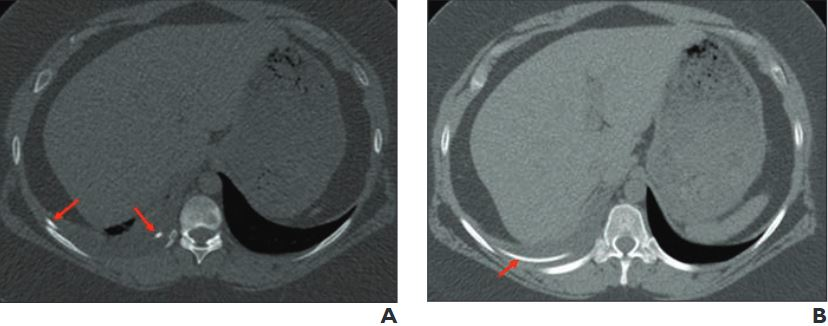

In one example, the AI model was provided with a photo of a patient’s arm with two lesions, which physicians would easily recognize as being caused by the same condition. Yet the lesions were presented at different angles, which caused the illusion of different colors and shapes, and GPT-4V failed to recognize that they could be related to the same diagnosis, NIH said.